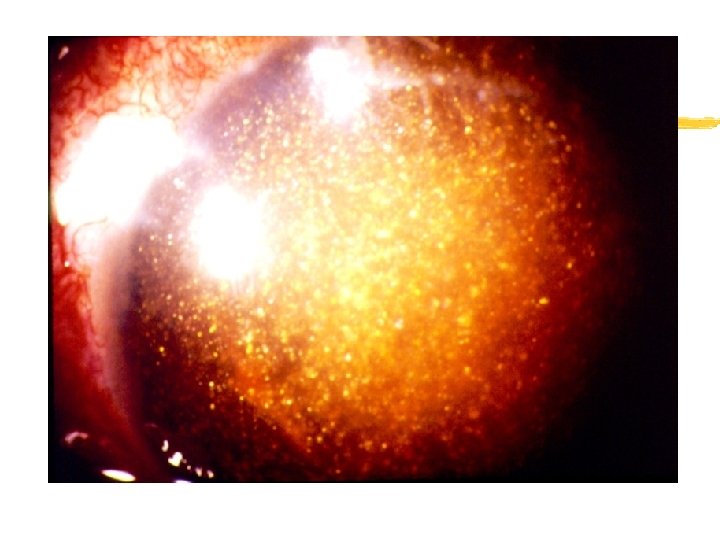

VII. PATHOLOGY AND AGE RELATED CHANGES y 2. Asteroid Hyalosis xa. hundreds of small spheres of calcium soaps are seen in the vitreous xb. are attached to the fibers of the vitreous so they move when the eye moves but always return to the same position xc. not associated with any systemic condition

VII. PATHOLOGY AND AGE RELATED CHANGES xd. more common in the elderly xe. no clinical significance xf. does not effect vision xg. 3 times more likely to be unilateral than bilateral

VII. PATHOLOGY AND AGE RELATED CHANGES y 3. Synchysis Scintillans xa. usually bilateral xb. cholesterol crystals in the vitreous that are not attached xc. not associated with any systemic condition xd. no loss of vision xe. usually occurs before 40